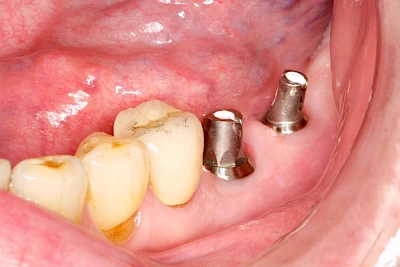

Implantate: Bestandteile

Implantate sind künstliche Zahnwurzeln. Nach einer gewissen Einheilzeit im Knochen (meist 3-6 Monate) erfolgt über einen separaten Aufbau (Abutment) die Befestigung einer Krone bzw. Brücke oder Zahnprothese.

Implantate haben im Gegensatz zu den eigenen Zähnen keine natürliche Abwehr und müssen deshalb besonders sorgfältig gepflegt werden.

Meist kommen als Materialien für Zahnimplantate Titanlegierungen oder zunehmend auch keramische Werkstoffe zum Einsatz.

In seltenen Fällen sind Implantate samt Aufbau aus einem Stück gefertigt. Auch gibt es Situationen, die ein Früh- oder sogar eine Sofortbelastung erlauben – dann kann die Einheilzeit der Implantate in den Knochen verkürzt oder sogar gänzlich darauf verzichtet werden.

"Stiftzahn" und "Implantat" ist nicht dasselbe! Bei einem Stiftzahn wird die Zahnkrone mit einem Stift in die noch vorhandene eigene Zahnwurzel zementiert. Ein Implantat im Gegensatz dazu ist selbst die (künstliche) Zahnwurzel, die dann weiter mit einem Zahnersatz versorgt wird.